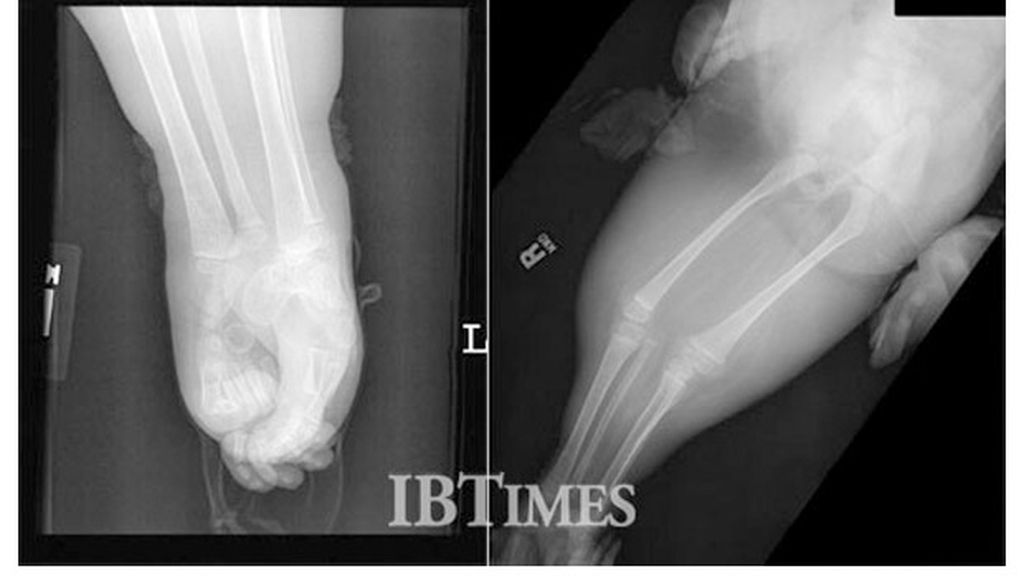

El difícil síndrome de la 'sirenomelia'

Una difícil operación

Las piernas de Shiloh Pepin